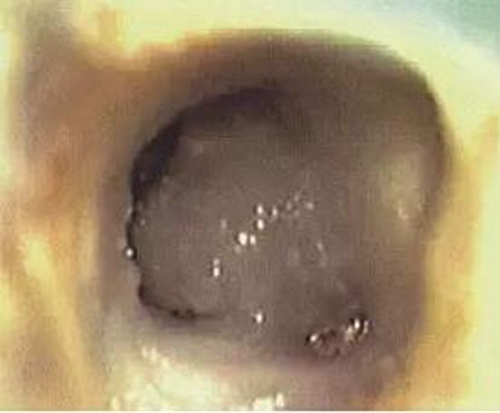

常規(guī)開髓后可在顯微鏡下看到髓室底有C形根管形態(tài),或呈C形(圖1),或呈分號形(圖2)。參考上期所涉及的C形根管分類圖進行診斷。

圖1 髓室底根管口呈C形

圖2 髓室底根管口呈分號形